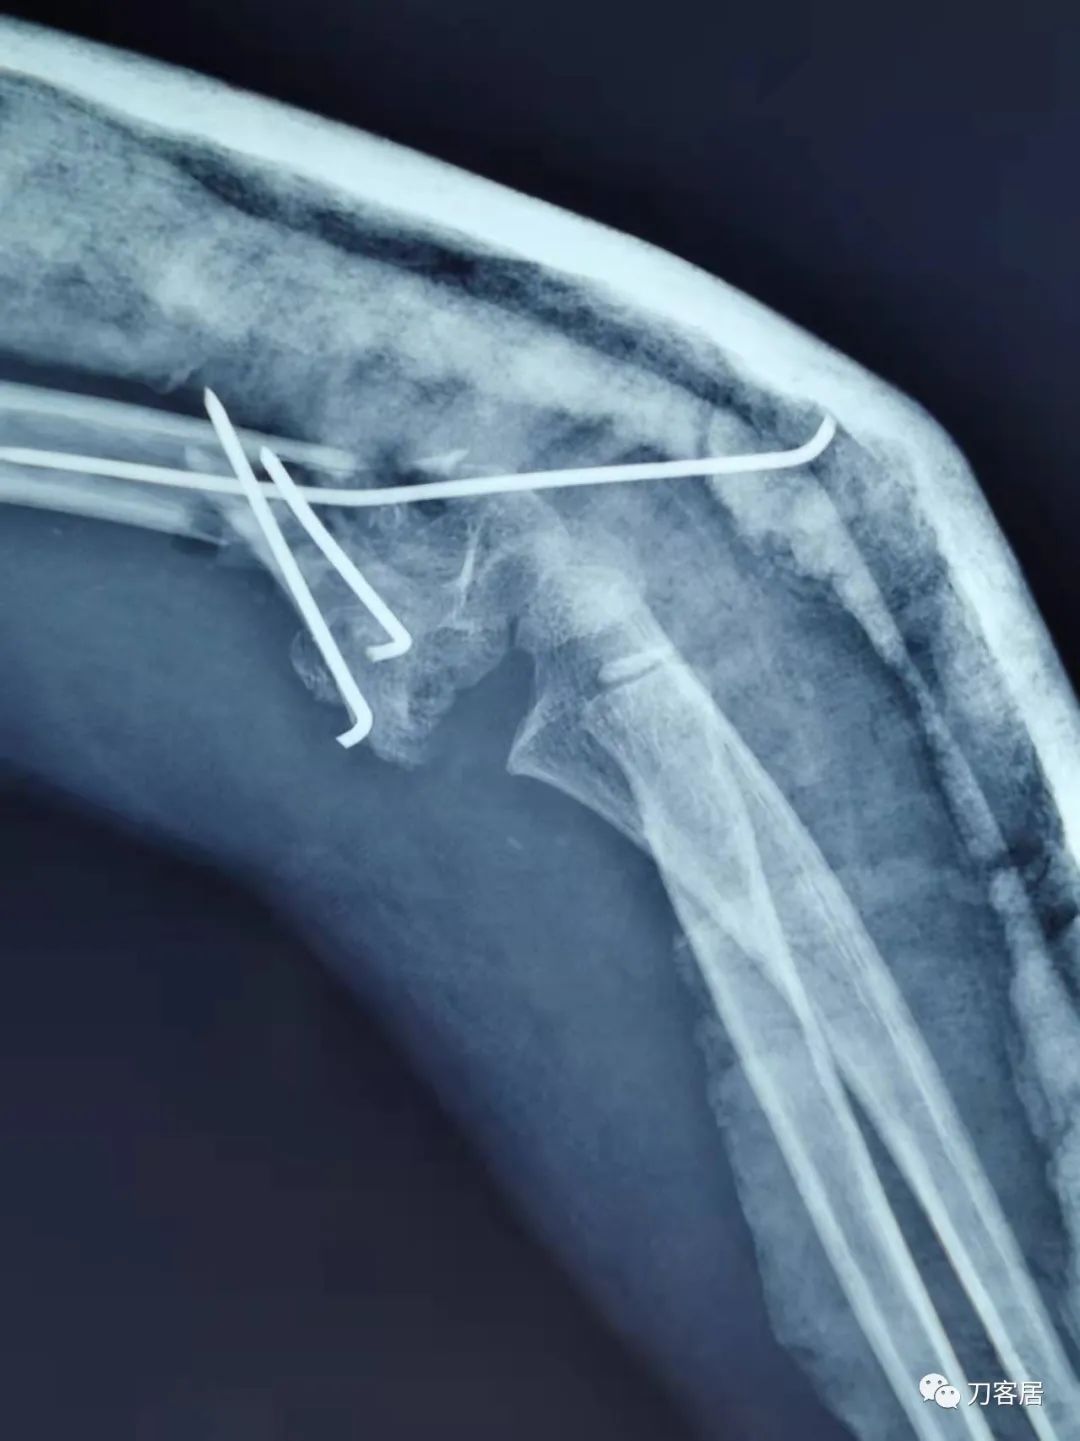

诊疗经过:2021年9月23日在全麻下行左肱骨髁间粉碎性骨折切开复位内固定术,术后予以抗感染、消肿止痛等对症治疗。

患者术后病情平稳,拍片复查示骨折对位对线良好,内固定在位。外固定稳妥。于2021年9月29日出院。

当地省中医院术后正位X线片

当地省中医院术后侧位X线片